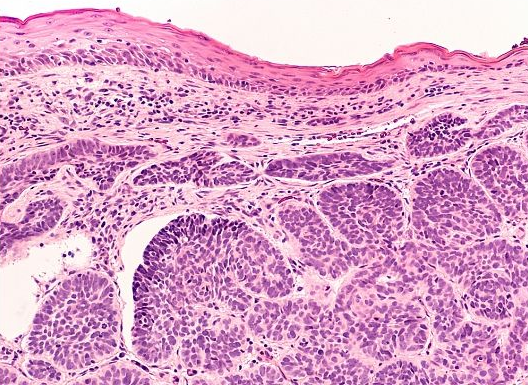

Histoloģija ir zinātne, kas pēta audus mikroskopiskā līmenī, un tās praktiskais lietojums medicīnā ir histopatoloģija, kas ļauj diagnosticēt dažādas slimības. Visbiežāk zināmā slimība, kas tiek diagnosticēta izmantojot histoloģiju, ir audzējs, tomēr šī nebūt nav vienīgā slimība, ko ļauj diagnosticēt šī medicīnas nozare

Kristīne Nevidovska apmeklēja dermatopatoloģijas kursu Austrijā